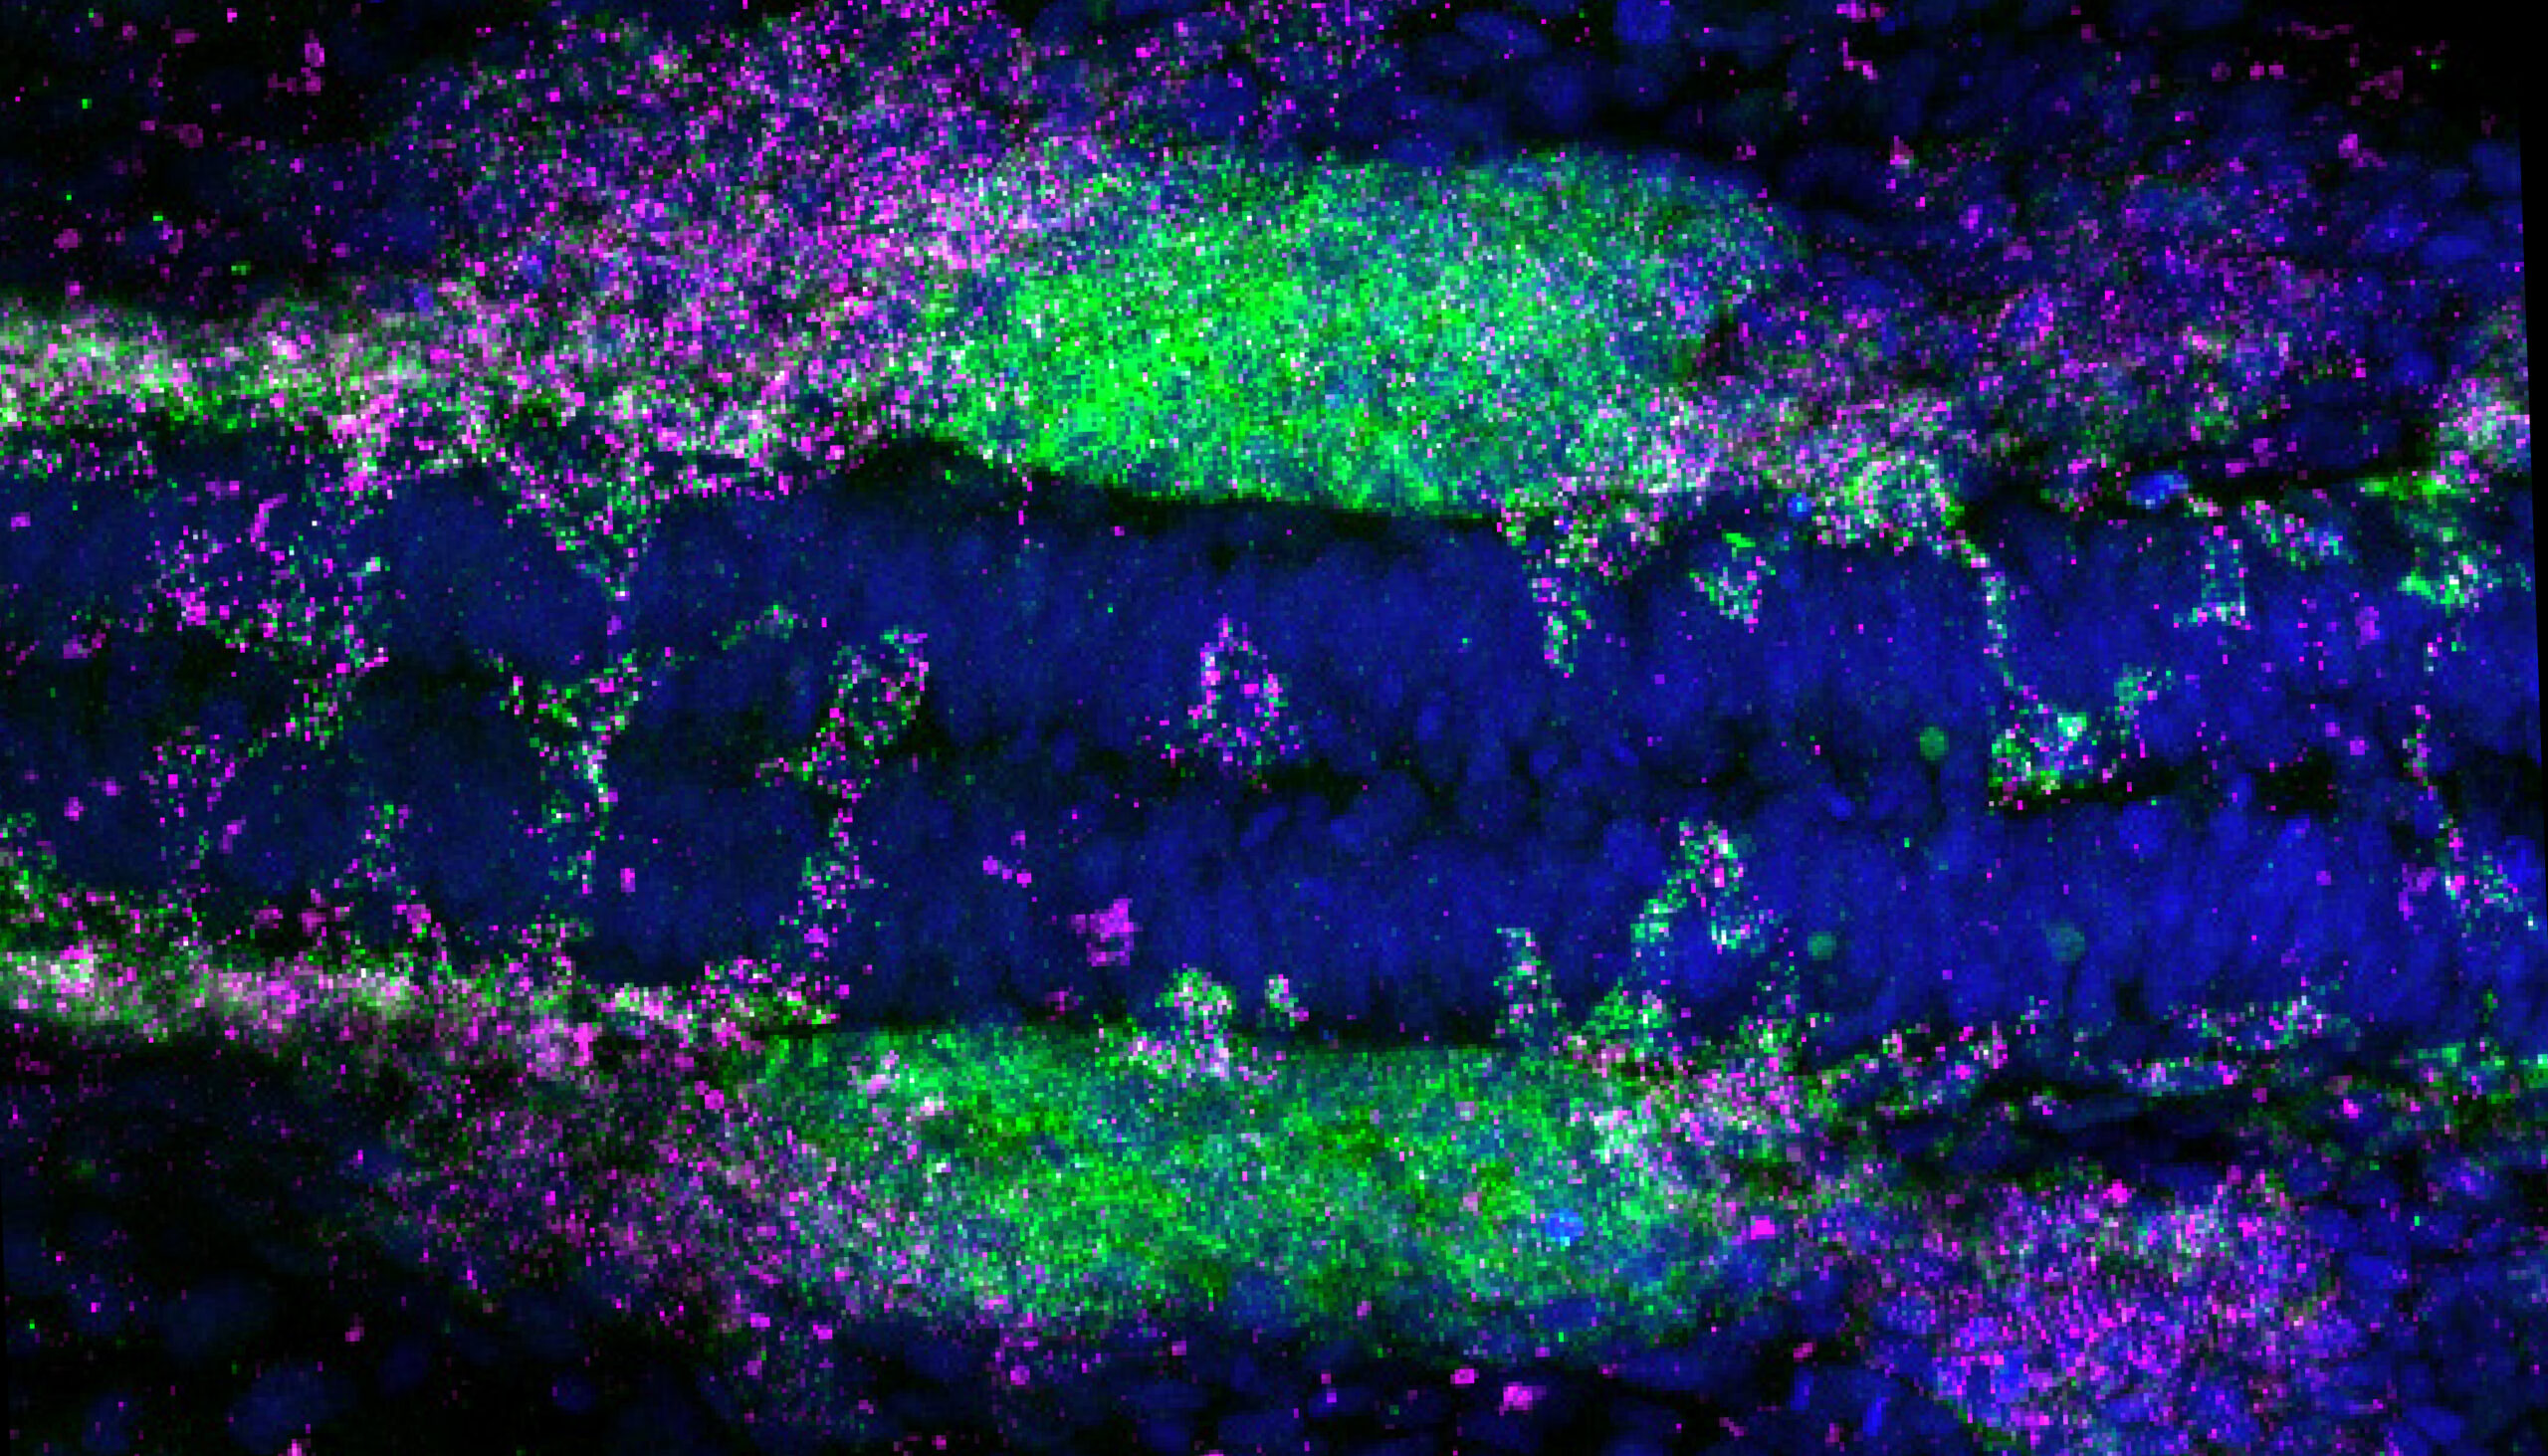

From COVID to cancer, new at-home test spots disease with startling accuracy

A new technology created by UC Berkeley engineers uses the “coffee-ring effect,” paired with plasmonics and AI, for rapid diagnostics.